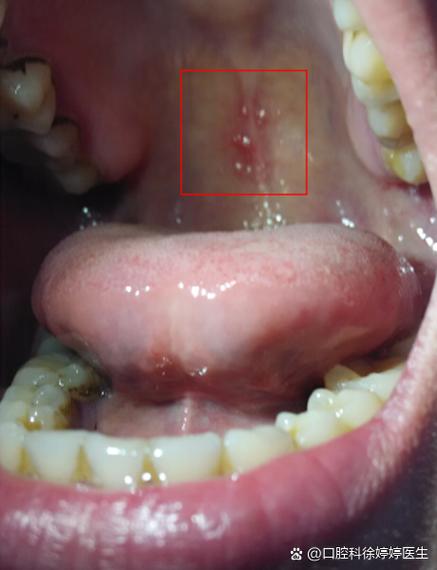

口腔上颚小凸起是疾病吗?

切牙乳头 (Incisive Papilla)

- 位置:位于上颚最前端,也就是门牙(切牙)正后方的那个圆润、稍微凸起的小肉球。

- 特点:它质地较硬,感觉像一个“小山包”,这是鼻腔和口腔在胚胎时期发育的遗迹,下面有丰富的神经和血管,它是完全正常的,也是上颚最明显的凸起。